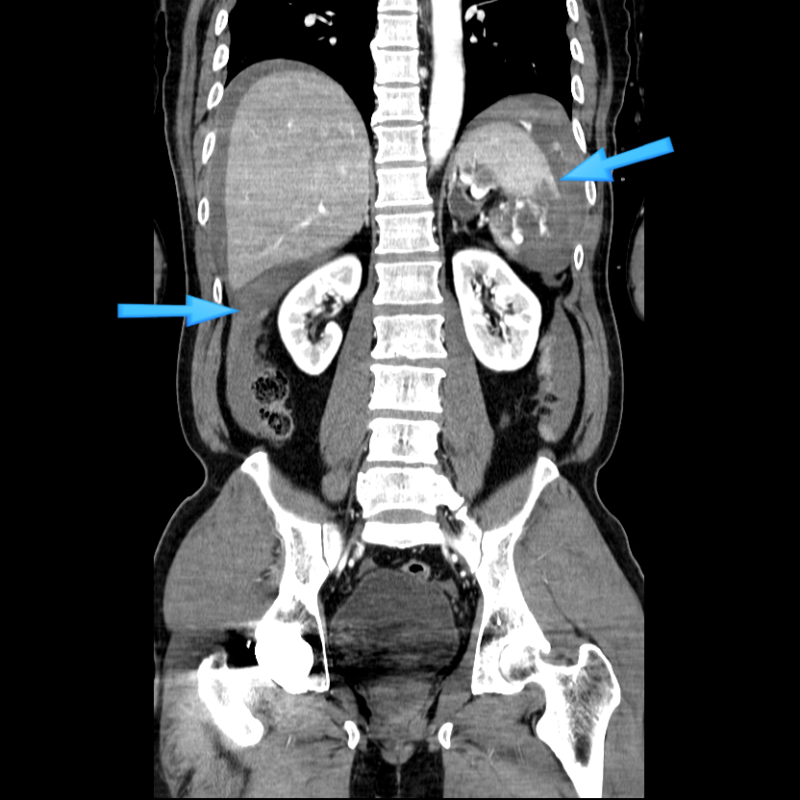

CT 검사를 통한 비장 파열의 진단, 응급 수술 : 네이버 블로그